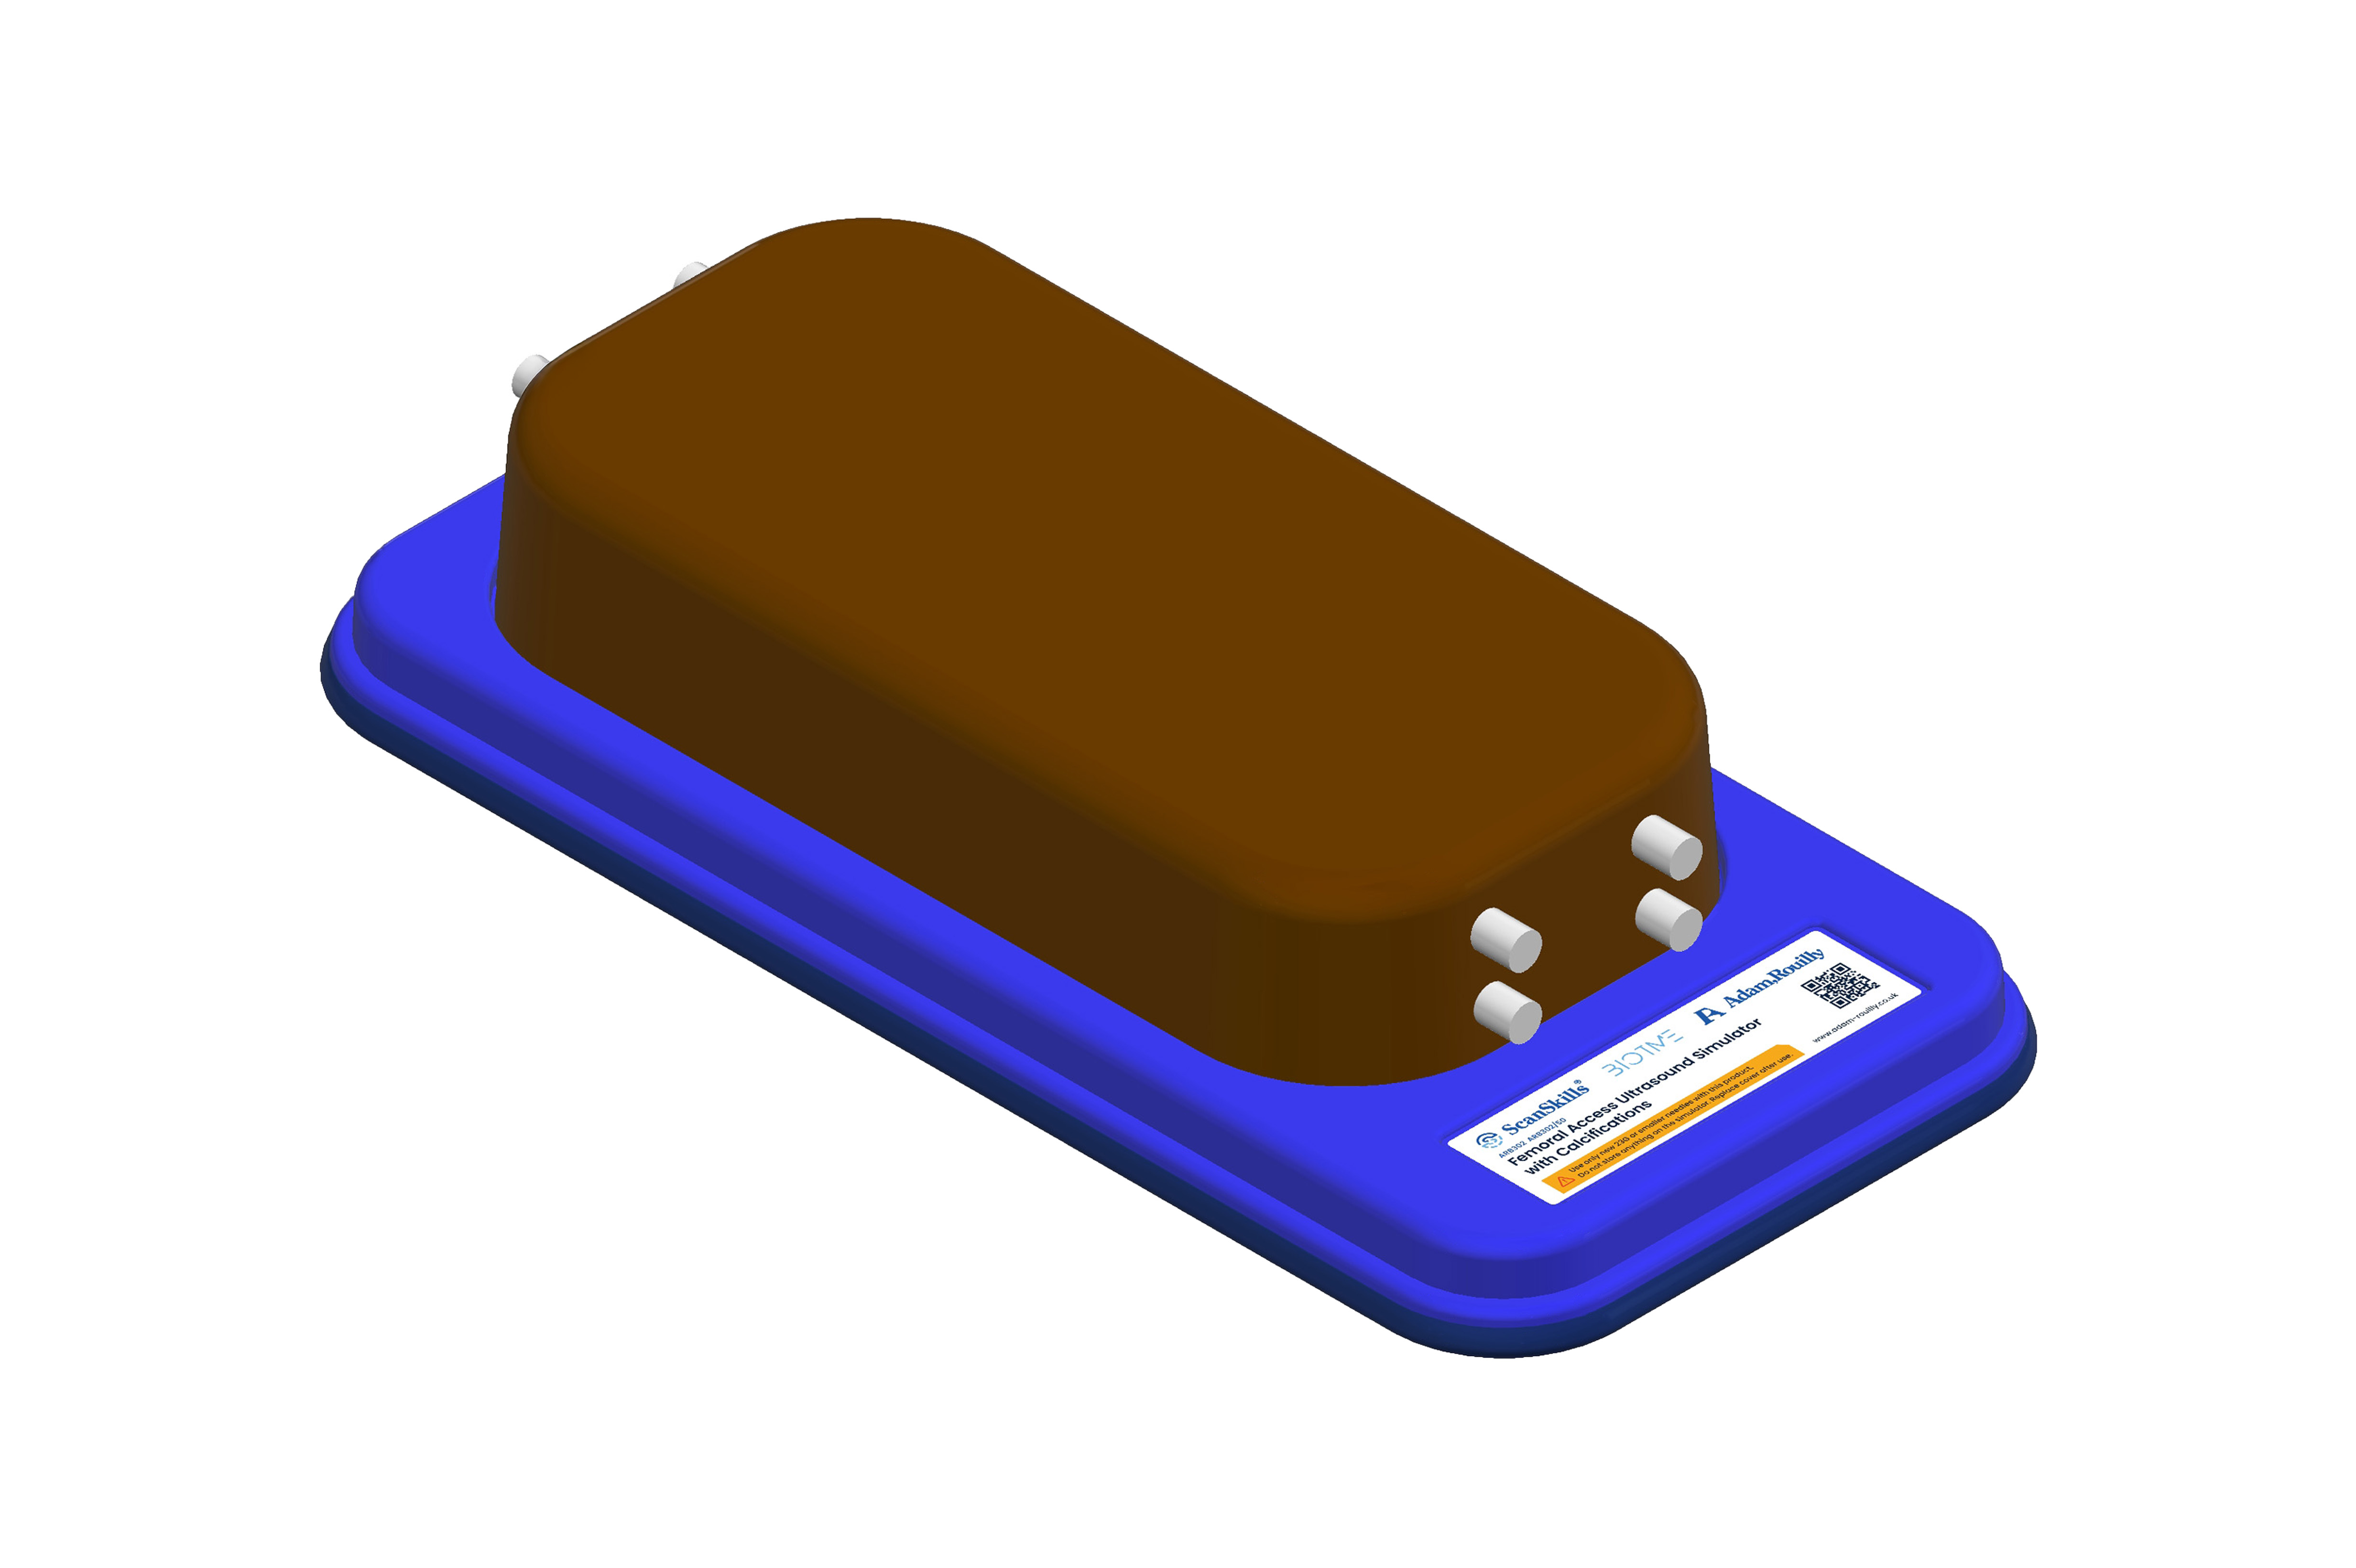

Femoral Access Ultrasound Simulator with Calcifications, Dark

Designed for femoral vascular access training, this simulator features two vertically branched veins (approx. 8 mm diameter, 20 mm deep) with simulated calcifications. Lifelike echogenic material closely mimics human tissue, enabling realistic ultrasound-guided practice, probe control, and anatomy recognition in a safe, repeatable environment for both trainees and experienced clinicians.

Our first release is the exceptional collection of BIOTME ultrasound trainers available in both light and dark skin tones.

These products are simple, powerful training devices which allow repeated, realistic practice of ultrasound guided invasive technique. Additionally, ultrasound machine proficiency, probe dexterity and recognition of anatomical structures can be learnt – all with minimal set up and maintenance.

BIOTME are constructed from a specialist material that mimics real human tissue both in feel and in its echogenic properties. On interventional models, needle traces disappear within a few days after practice (when used with 23G or smaller needles) – enhancing both the realism and cost-effectiveness of these trainers. The materials used in the BIOTME collection are fully recyclable and can be returned to us when the time comes to replace them.

Features

- For femoral access with two vertically branched blood vessels with simulated calcifications

- Veins of diameters approximately 8 mm, located 20 mm below the surface of the simulator for vascular access

- Soft, realistic echogenic material which mimics human tissue

- Highly mobile all in one trainer on a base with Protective storage cover

- Size (base and lid L/W/H) 401.7, 191.5, 87.2 mm

- BIOTME ultrasound simulator mounted on a base

- Protective storage cover